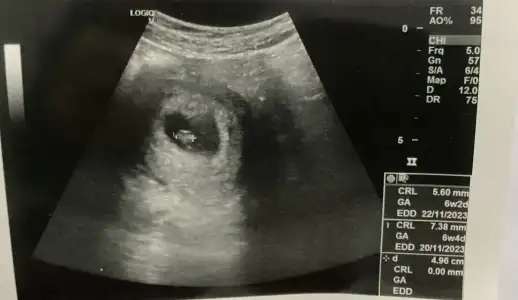

Sanırım bu teori en merak ettiğim teoriBence bebeğin konumu değişebiliyor o yüzden parlak alana odaklanmalıyız. Seninkinde bebek sağdaydı ama parlak alan net olarak sağda mıydı bi bakar mısın :) Kendimizi geliştirelim![]()